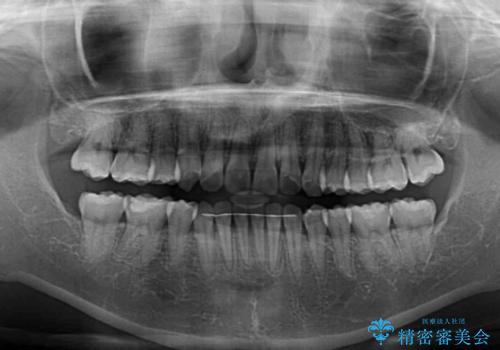

八重歯の抜歯矯正 補助装置とワイヤーを併用したインビザライン矯正治療

骨格的に下顎が左側に変位していたため、上下正中を合わせることは困難であることは分かっていましたが、可能な限り合わせることができました。

骨格的なズレがあると仕上げの段階で奥歯の咬み合わせが不安定となるため、予定よりやや長期間となりました。